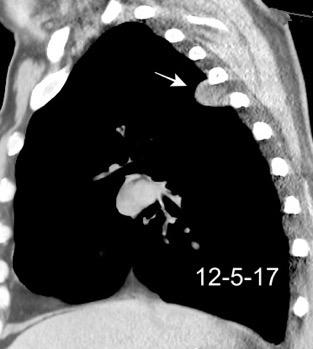

Marzo 2014: Perforación longitudinal distal secundaria a episodio de vómito (síndrome de Boerhaave). Derrame pleural izdo. que evoluciona a empiema.

Wang C-T et al. Tension hydropneumothorax in a Boerhaave syndrome patient: A case report . World J Emerg Med, 2021. Katabathina V et al. Nonvascular, nontraumatic mediastinal emergencies in adults:a comprehensive review of imaging findings. Radiographics. 2011.